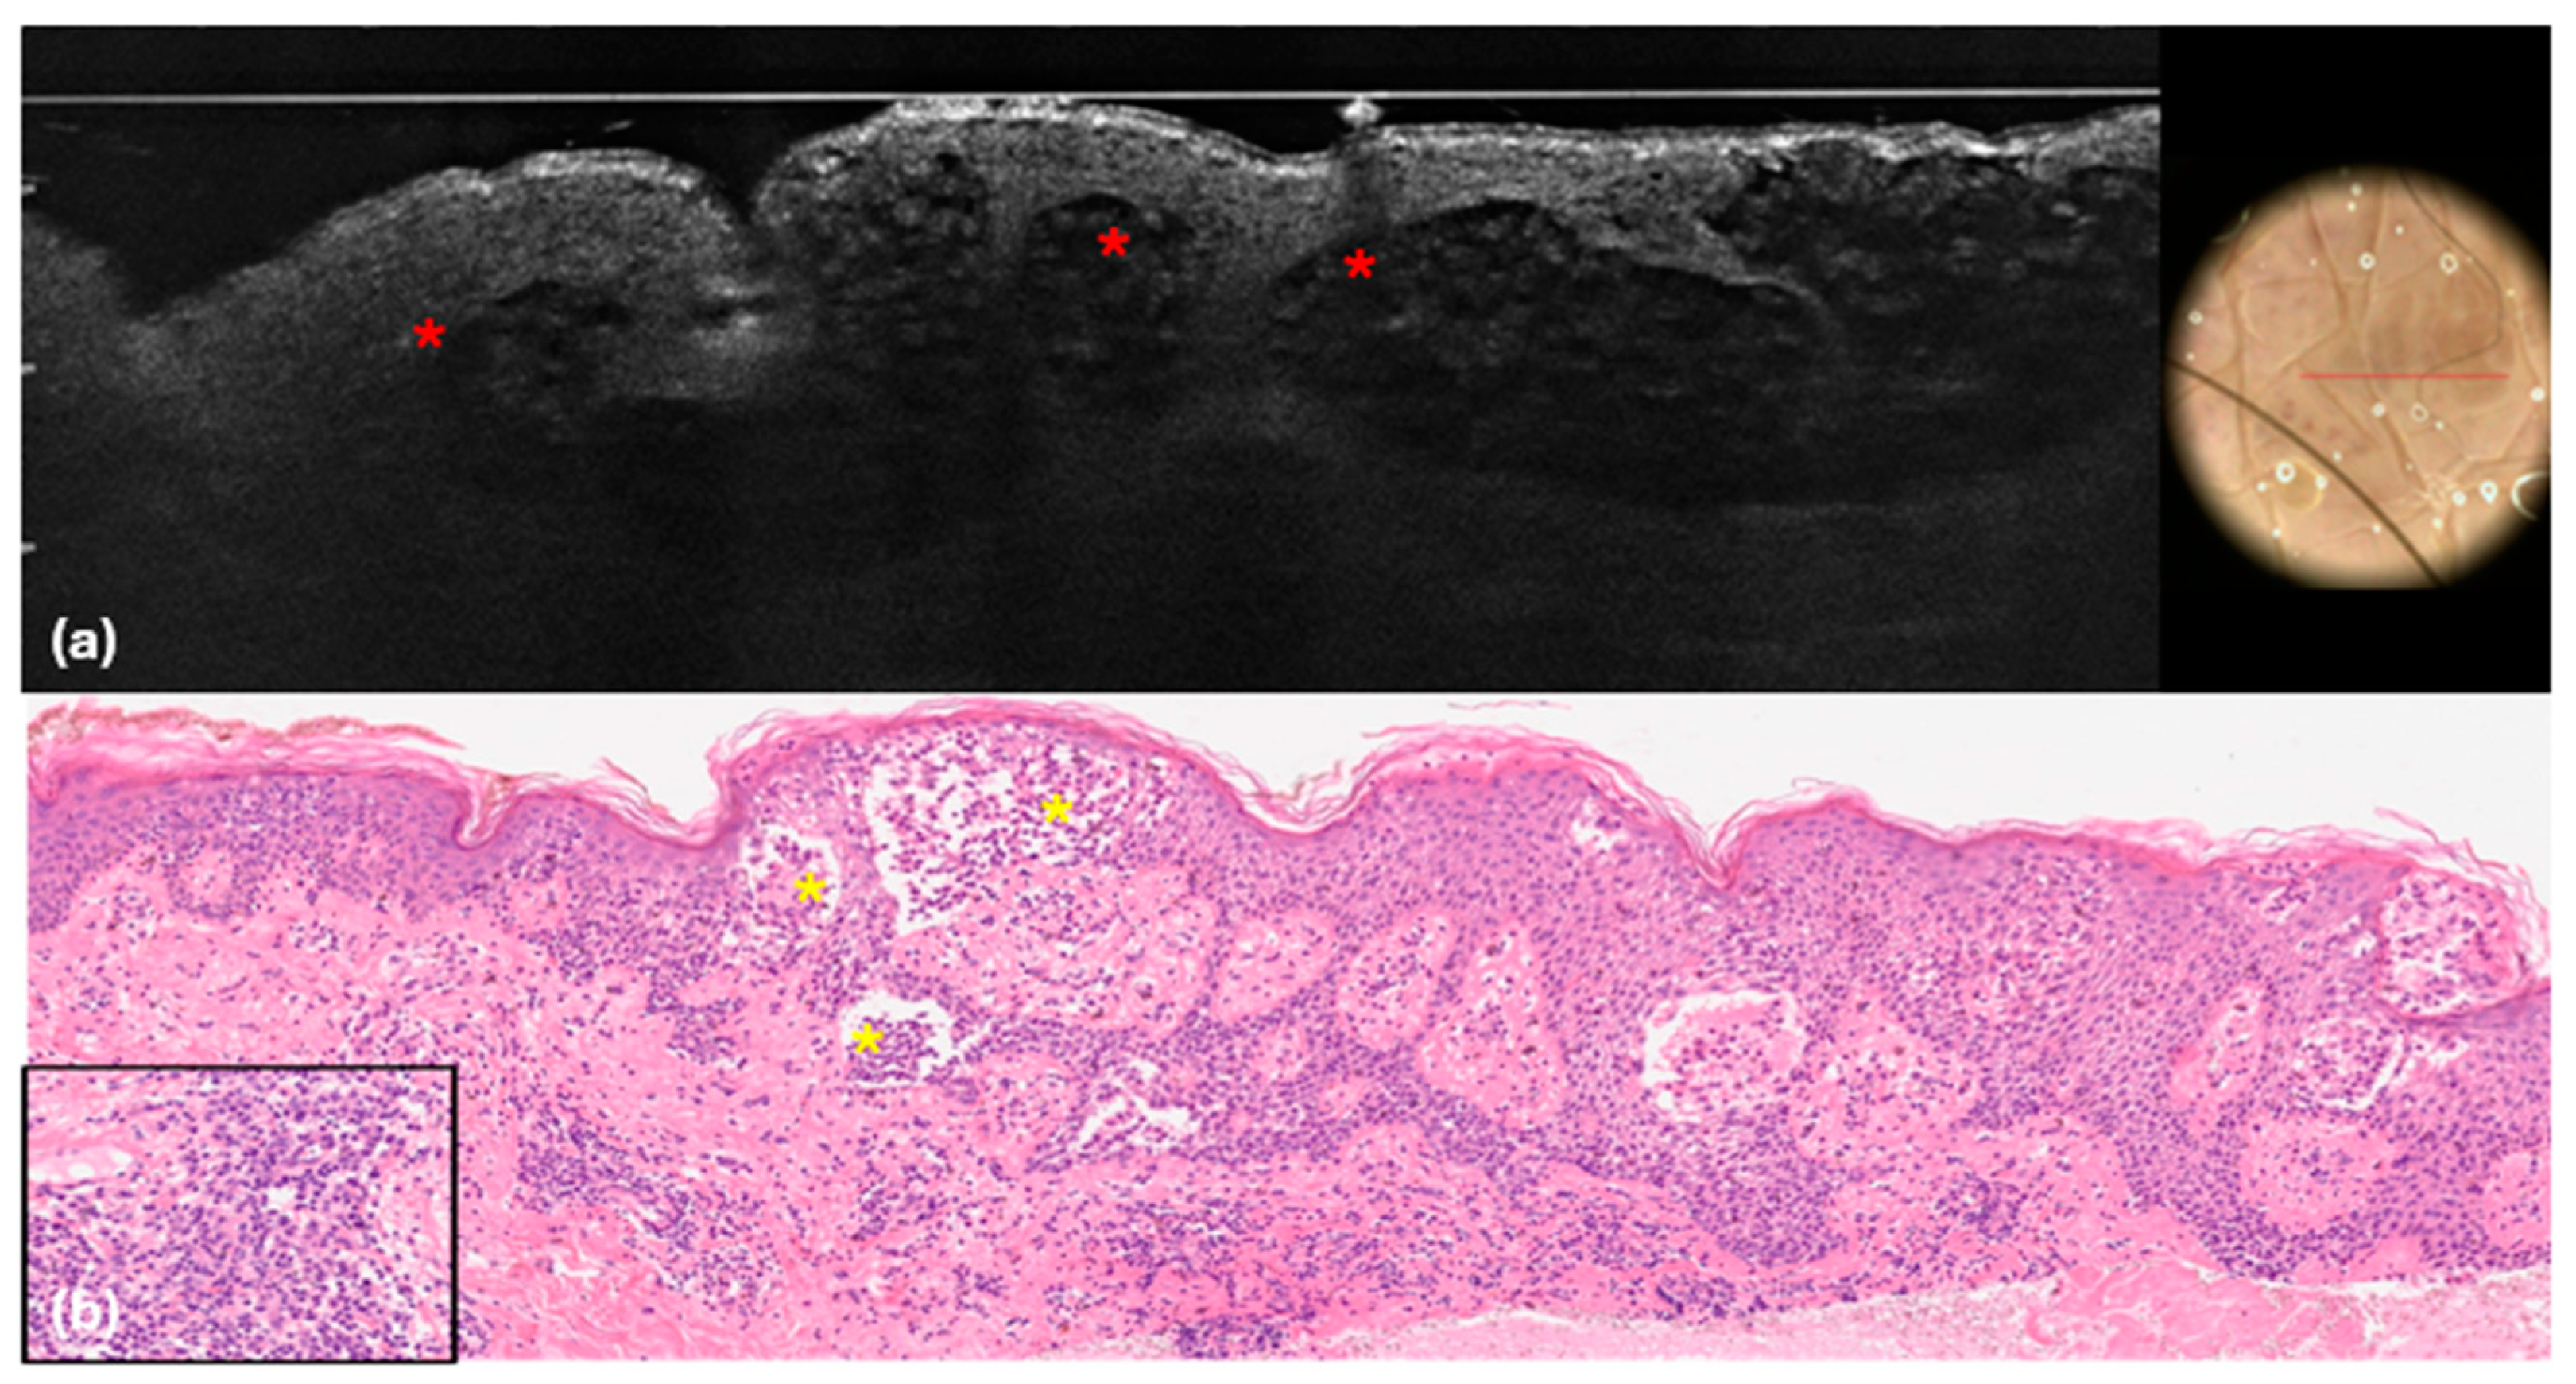

| Lymphocyte infiltration Well-defined hypo-reflective areas filled with hyper-reflective round cells 5 to 10 μm in diameter inside of the dermis. At RCM these areas can be delineated by hyper-reflective collagen bundles. |